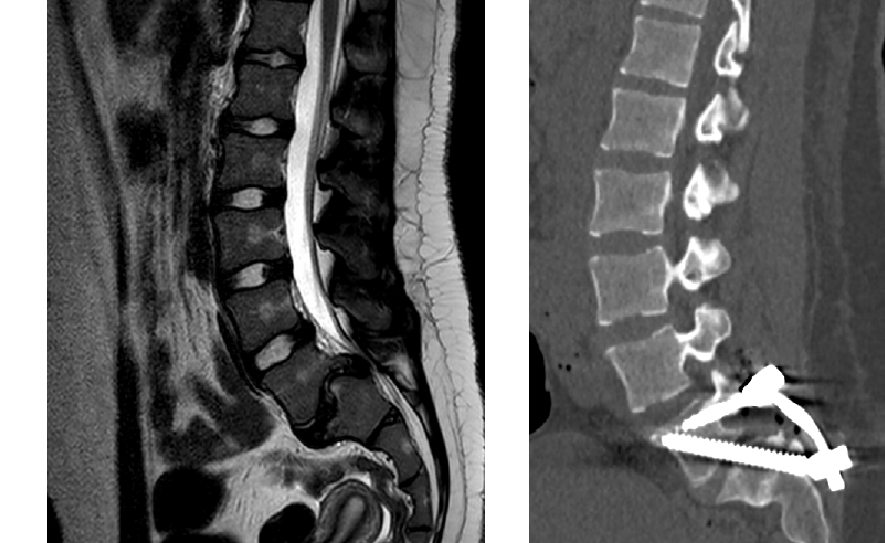

Technical capabilities: minimally invasive and reconstructive surgery technologies, bone plastic materials and instrumental fixation, modern power and ultrasound surgical equipment, navigation, neuromonitoring.

Main areas of surgical work: